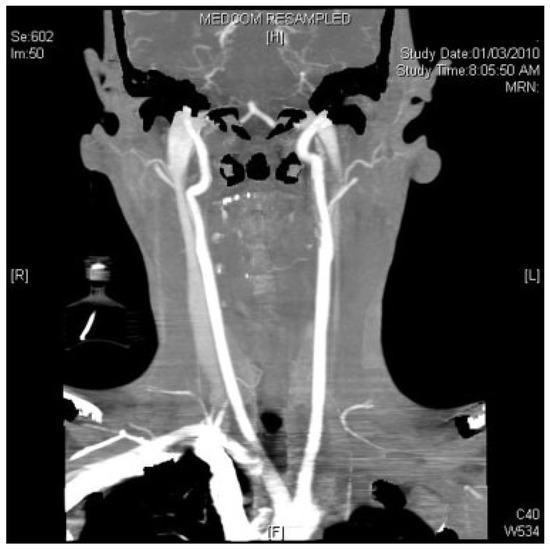

During surgical exposure of the left subcondyle (exposed via a preauricular approach), brisk hemorrhage was encountered that did not stop with direct pressure. The vascular service was consulted and the left external carotid artery was exposed through a neck incision. A silicone vascular loop served as a sling for control of bleeding. Following this, the preauricular wound was again explored and a longitudinal laceration of the maxillary artery was seen. It was probable that this laceration was in contact with the sharp edges of the mandible fracture. The maxillary artery was subsequently surgically ligated and the fracture fixation proceeded un- eventfully. A CT arteriogram of the external carotid artery performed on the first postoperative day confirmed the ligation of the maxillary artery (Figure 3). Distal reconstitution of the arterial flow was observed, and no false aneurysm was seen.

Figure 3. Computed tomographic (CT) arteriogram of the external carotid system done 24 h after the surgery confirming successful ligation of the maxillary artery.